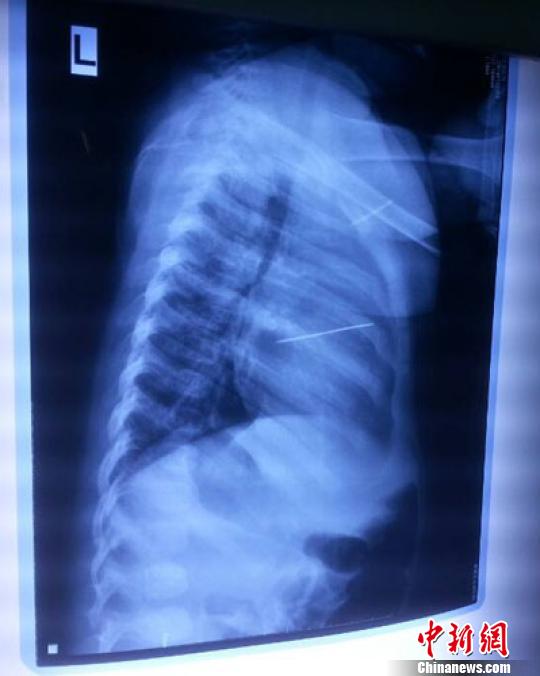

女嬰胸片提示心臟里面扎了一個(gè)縫衣針 蔡迅翔 攝

醫(yī)院胸心外科主任翟波介紹說,1月22日,小患者彤彤因?yàn)榘l(fā)燒抽搐來醫(yī)院就診,常規(guī)檢查時(shí)發(fā)現(xiàn)孩子心臟里面扎了一個(gè)縫衣針。

“第二天上午,我們做了個(gè)緊急彩超檢查,發(fā)現(xiàn)針是從患者右心室表面刺入,穿破室間隔,到達(dá)左心房,中間還有一部分損害到二尖瓣。于23號(hào)下午,我們就做了一個(gè)緊急手術(shù),手術(shù)中發(fā)現(xiàn),這枚針已經(jīng)刺入心臟,沒入了右心室的下面,表面已經(jīng)看不到針了,僅能看到一個(gè)小針眼,還在往外滲血,一點(diǎn)一點(diǎn)的滲,心包腔里面大概有100多毫升的出血,心包上一個(gè)洞,針在右心室表面刺入以后,穿過室間隔,在二尖瓣的上方,進(jìn)入了左心房,在針的四周,有很多纖維沉積物,包繞著這枚針?!钡圆ㄕf,他們把針取出來以后,測(cè)量了一下,長(zhǎng)度大概是五厘米,同時(shí)發(fā)現(xiàn)這個(gè)針給患者左心房的后壁造成了一定的損傷,左心房的后壁已經(jīng)損傷了三分之二,還剩下有左心房的外膜,很薄的一層,如果這一層再破的話,這個(gè)孩子將會(huì)引起大出血,很快就會(huì)死亡。